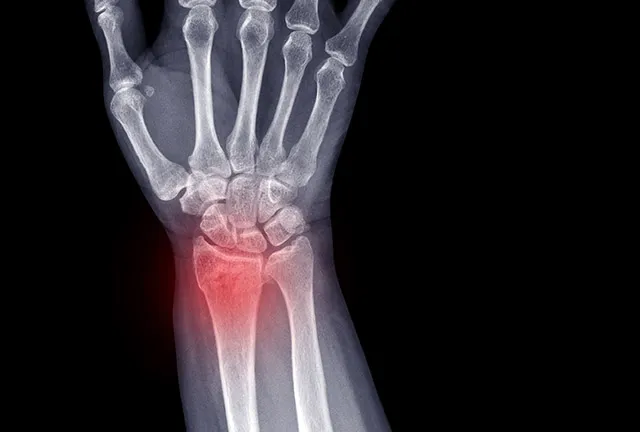

Złamanie nadgarstka to jedno z częstszych urazów kończyny górnej, które potrafi skutecznie wyłączyć nas z codziennych aktywności. Wiem z doświadczenia, jak wiele pytań pojawia się w głowie pacjenta w takiej sytuacji przede wszystkim: "Jak długo to potrwa?" i "Co muszę zrobić, żeby wrócić do pełni sił?". Ten artykuł ma za zadanie kompleksowo odpowiedzieć na te wątpliwości, prowadząc Cię przez meandry rekonwalescencji i rehabilitacji, abyś mógł świadomie i aktywnie uczestniczyć w procesie powrotu do zdrowia.

Kiedy pacjent trafia do mnie po złamaniu nadgarstka, pierwsze pytanie, jakie słyszę, to zazwyczaj: "Kiedy wrócę do normalności?". Odpowiedź nigdy nie jest prosta i jednoznaczna, ponieważ czas rekonwalescencji to bardzo indywidualna kwestia. Mogę jednak powiedzieć, że średni czas aktywnej rehabilitacji po zdjęciu unieruchomienia wynosi zazwyczaj od 6 do 12 tygodni. Pełny powrót do sprawności, zwłaszcza w przypadku bardziej skomplikowanych urazów, może jednak trwać znacznie dłużej od 3 do 6 miesięcy, a w niektórych przypadkach nawet rok.

- Złamania z przemieszczeniem, wieloodłamowe czy śródstawowe to zupełnie inna bajka. Często wymagają one interwencji chirurgicznej, a proces gojenia i odbudowy funkcji jest znacznie dłuższy. W praktyce często spotykamy się ze złamaniami Collesa i Smitha, które dotyczą dalszej nasady kości promieniowej i mogą mieć różny stopień skomplikowania.